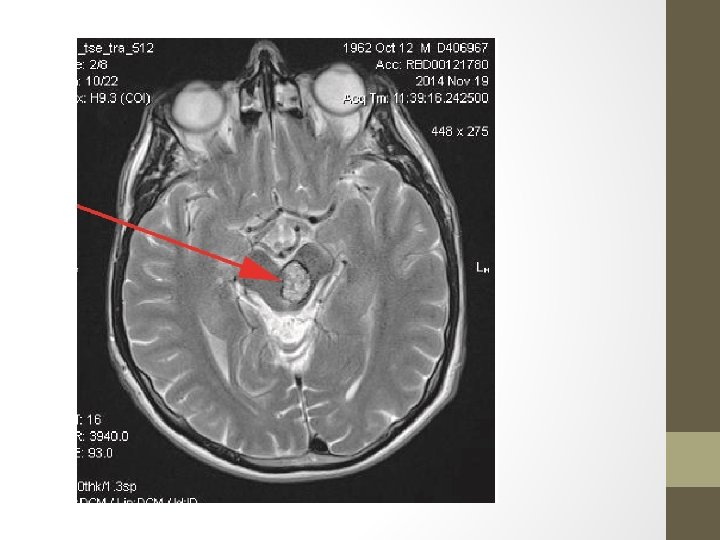

Cavernous Malformations • Mostly single lesions • Multiple lesions may be familial and screening of family members may be indicated (familial multiple cavernous malformation syndrome) • Along with capillary telangiectasias, are commonly seen following cerebral radiotherapy • Mostly asymptomatic- or hemorrhage and seizures • Composed of a "mulberry-like" cluster of dilated thin-walled capillaries, with surrounding hemosiderin. (Unlike AVMs, there is no normal brain between the interstices of these lesions. ) • %80 supratentorial • Characteristic popcorn appearance in MRI • Symptomatic lesions should, when possible, be resected and complete resection is curative